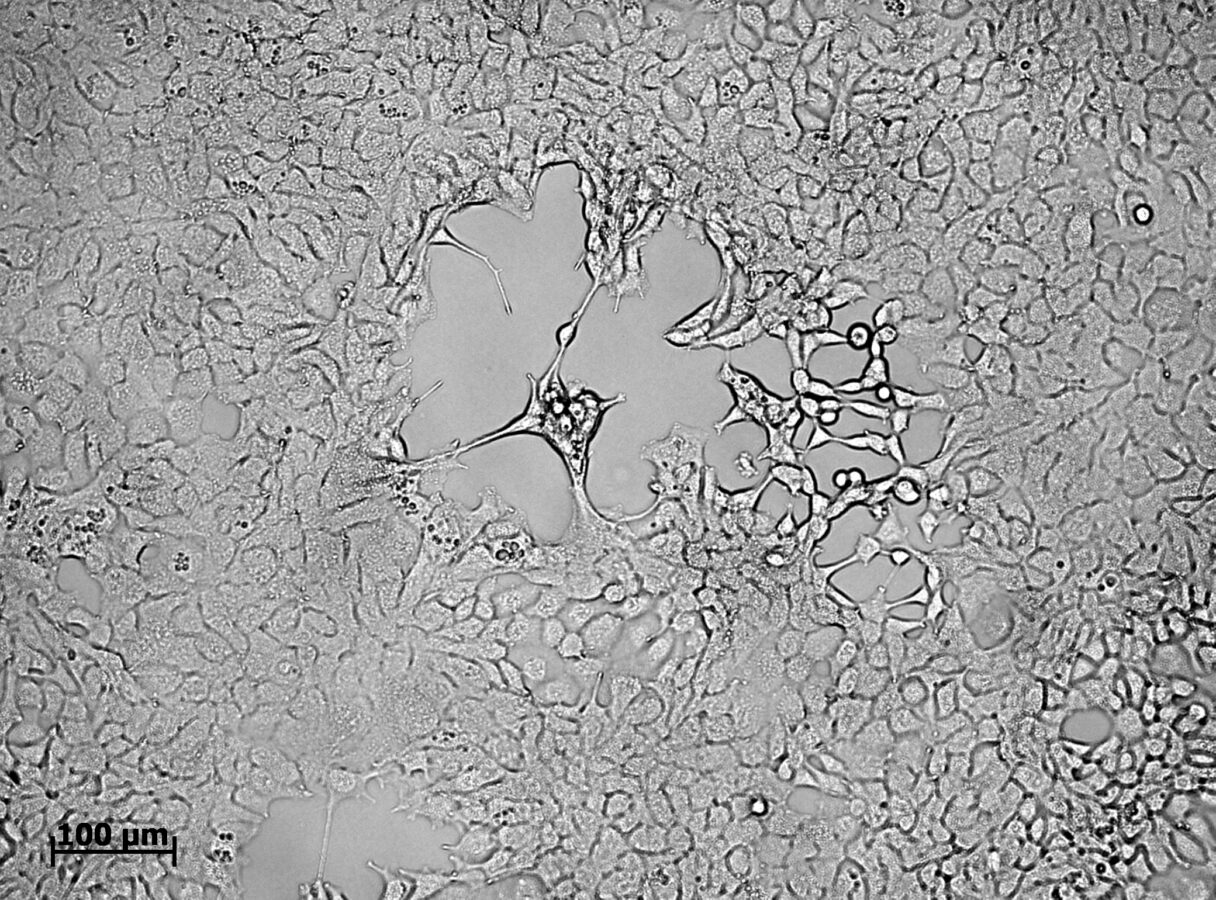

Изображение: аутофлуоресценция липофусциновых гранул в клетках пигментного эпителия сетчатки. Микрофотография получена с помощью лазерного сканирующего микроскопа.

Именно эту проблему решил коллектив ученых из МГУ и ИБХ: предложено измерять время жизни флуоресценции липофусциновых гранул с помощью лазерной спектроскопии с пикосекундным разрешением. При воздействии синим светом этот параметр увеличивается параллельно с ростом токсичности липофусцина. Используя подобные зависимости, можно устанавливать степень агрессивности липофусциновых гранул, что может быть использовано в диагностических целях.

«Примечательно, что этот метод применим и для контроля эффективности новых способов нейропротекции сетчатки при ВМД, активно разрабатываемых в настоящее время, – утверждает научный сотрудник лаборатории физико-химии биологических мембран биологического факультета МГУ Светлана Сидоренко. – Один из таких способов, предложенный нашим коллективом, основан на восполнении уровней природных антиоксидантов глаза – каротиноидов (лютеина, зеаксантина) – за счет их доставки к сетчатке с помощью уникального транспортного белка AstaP, обеспечивающего их растворимость и, как следствие, высокую биодоступность. Применение этого комплекса действительно предотвращает увеличение времени жизни флуоресценции липофусциновых гранул в клетках пигментного эпителия, то есть делает их существенно менее опасными. Мы надеемся, что внедрение всех упомянутых методов позволит существенно улучшить диагностику ВМД и замедлить прогрессирование этого серьезного заболевания».